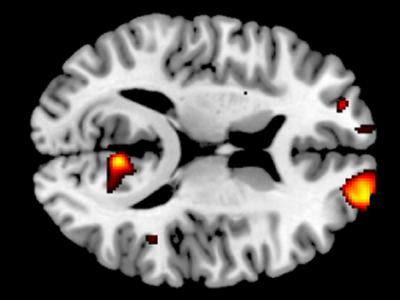

大脑扫描可一定程度预测人的智力

圣路易斯华盛顿大学的科学家研究表明,个体智力的部分差异与连接左侧大脑前额皮质...

研究表明一个人大脑中的灰质越多越无私

科学家发现大脑内顶叶和颞叶结合处有更多灰质的人更无私 瑞士苏黎世大学的研究人...